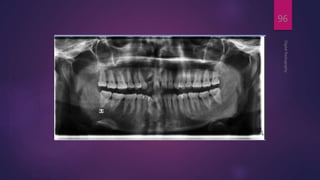

Negative Conversion

 Useful in visualizing the trabecular pattern of bone

 pulp canal and chamber anatomy

DigitalRadiography

96